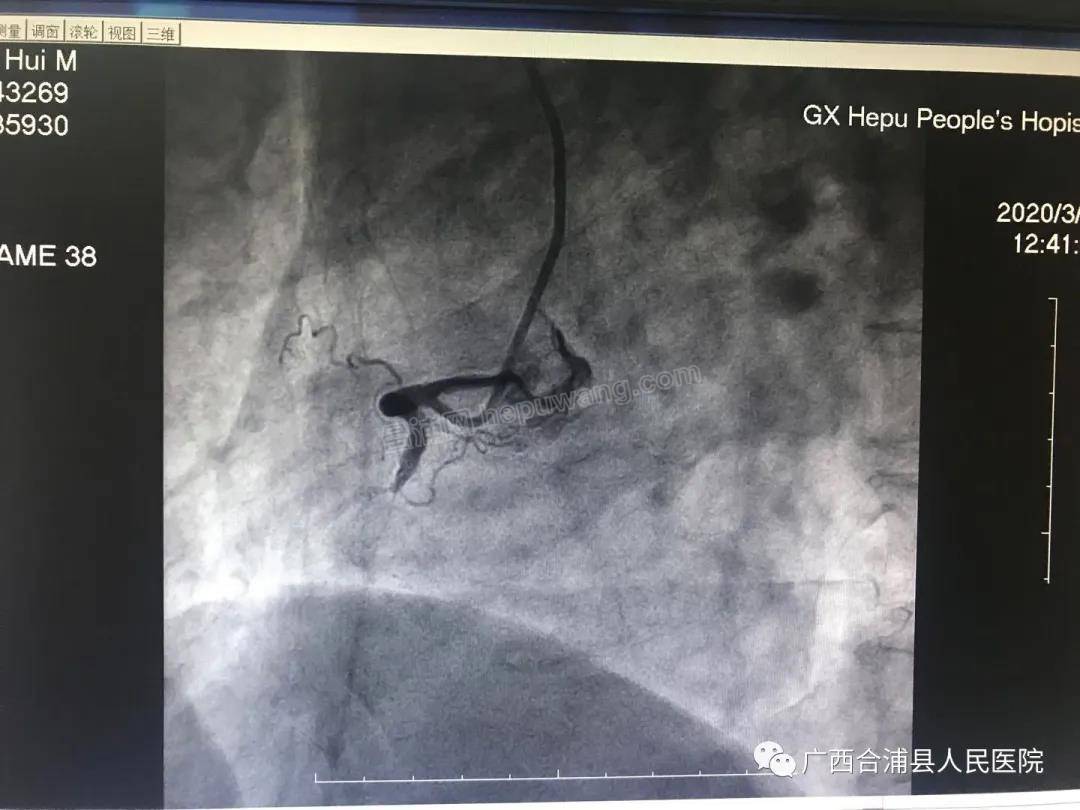

冠脉造影显示为右冠近段完全闭塞,情况非常紧急,必须马上开通闭塞的血管!手术过程惊心动魄,患者病情变化之快始料未及,刚完成冠脉造影,患者的血压骤降至80/50 mmHg,心率45次/分,期间反复出现13次室颤,甚至还出现心脏骤停。“患者出现室颤,神志不清,给予双相波200焦耳非同步电流进行电除颤;立即给予阿托品提高心率,多巴胺、阿拉明升压;患者再发室颤,静推胺碘酮对抗......”心内科主任赖美声组织团队为患者提供高级心血管生命支持, “莫小燕(副主任医师)负责电除颤,黄齐海(主治医师)进行心外按压,袁翠玉(护师)负责气道管理,黄祖霞(护师)负责静脉通道管理......”在团队的密切配合和支持下,廖伟杰及助手邹旭主治医师心无旁骛快速植入2枚支架开通了闭塞血管,患者室颤得以停止,恢复正常心律。13时25分,患者安返病房。